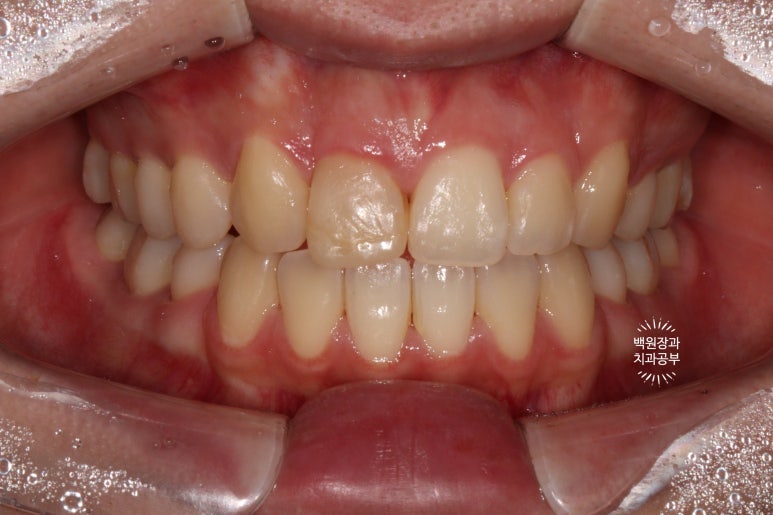

오늘 소개해드릴 환자분은 다소 보기 드문, 앞니가 하나 없어 교정치료를 받았던 20대 여자 환자분입니다.

잇몸 성형과 치아미백 그리고 지르코니아 크라운을 이용해 앞니를 예쁘게 만들어 본 케이스입니다.

어렸을 때 대문니를 하나 뺐어요.

인접한 작은 앞니에 레진을 붙여 사용하고 있었어요.

앞니가 하나 없어 대문니 없이 교정치료를 마무리하신 상태입니다.

사실 전문가가 아니면 딱 보고 뭐가 문제지?? 라고 생각하실 수도 있을텐데요,